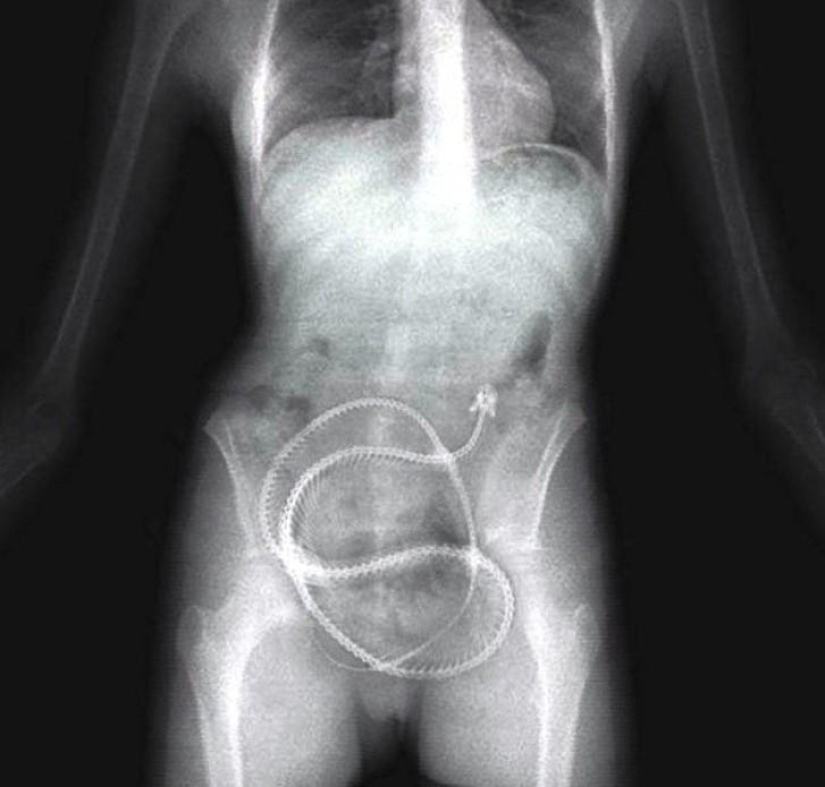

19. Springs from the bed.

22. Surgical forceps.